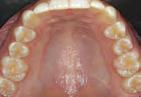

Figura 1. Fotografia inicial, se observa un fenotipo delgado festoneado, estrecha banda de encía queratinizada en zona anteroinferior con sobremordida, apiñamiento y retroinclinación en el maxilar anterior inferior.

Paciente femenino de 13 años de edad, acude con sus padres a la clíni ca de periodoncia de la Universidad Popular Autónoma del Estado de Puebla para revisión dental. Al reali zar la exploración clínica, en su aná lisis gingival, la paciente presenta un fenotipo gingival delgado, con estre cha banda de encía queratinizada en el maxilar anteroinferior, edema y eri tema en zona marginal y papilar, acu mulación de biofilm dental en zonas interproximales y marginales, retroin clinación y apiñamiento anteroinfe rior, con una notoria sobremordida y paladar profundo. Posteriormente al realizar periodontograma y aná lisis radiográfico se diagnostica a la paciente con una gingivitis inducida por biofilm dental y según la nueva clasificación del World Workshop del 2017 presenta deformidad mucogin gival alrededor de los dientes por la estrecha banda de encía queratiniza da (Figura 1).